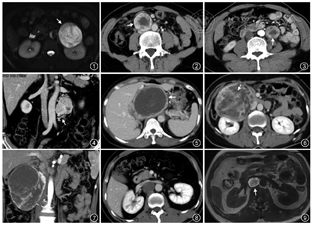

1.嗜铬细胞瘤:为肾上腺髓质最常见的肿瘤,好发年龄20~50岁。功能性嗜铬细胞瘤可分泌儿茶酚胺(去甲肾上腺素和肾上腺素),患者临床常表现为儿茶酚胺一过性升高引起的阵发性高血压、间歇性头痛、出汗、心悸等症状。临床上依据生化检测血浆或尿液中儿茶酚胺或其代谢物VMA和3-甲氧基肾上腺素水平升高来辅助诊断嗜铬细胞瘤。嗜铬细胞瘤的“10%法则”:10%为多发、10%为恶性、10%为双侧、10%发生于肾上腺外、10%为家族性或与神经外胚层综合征相关、10%为无功能性肿瘤[5]。嗜铬细胞瘤CT和MRI表现为富血供肿块,肿块较大时可不均质、伴内部出血。肿块典型MRI表现为T2WI高信号(图1)。

2.腹膜后肾上腺外副神经节瘤:好发于30~50岁患者,无明显性别差异,多为功能性肿瘤;占腹膜后肿瘤的1%~3%,可发生于腹膜后任何部位,好发于肾动脉至腹主动脉分叉水平的主动脉旁区域,最常见于Zuckerkandl体(图2,3),即肠系膜下动脉起始处与腹主动脉分叉之间[3]。不同部位肾上腺外副神经节瘤的影像学特征类似。良性肿瘤体积常较小,密度均匀。较大的肿瘤呈椭圆形或分叶状边界清楚的软组织肿块,常伴坏死和出血(图2~7),有时可见出血所致液液平面(图3)。副神经节瘤为富血供肿瘤,增强后明显强化,动脉期显著,肿块周围或实性成分内可见迂曲增粗的肿瘤血管[6, 7]。少数因肿瘤内大量出血或坏死呈低强化或无强化(图8,9)。钙化较常见,发生率约15%。肿瘤T1WI上呈等或低信号,内部出血区呈高信号(图9);T2WI上信号不均匀,可呈显著高信号;表观扩散系数相对于神经鞘瘤和颈部副神经节瘤更高[8]。此外,应仔细观察有无多发副神经节瘤(图10, 11, 12, 13)。

3.恶变、转移及预后:副神经节瘤具有一定的恶变及转移潜能,恶变率2%~10%,恶性肿瘤常较大,内部见低密度坏死区。恶性副神经节瘤可通过淋巴或血行转移播散至区域淋巴结、骨、肝、肺等部位。腹膜后肾上腺外副神经节瘤侵袭性更强,多达42%的病例发生转移[3],而嗜铬细胞瘤转移发生率仅2%~10%。不存在嗜铬性组织的部位如果出现肿瘤灶,则诊断为转移性病灶。组织病理学难以界定良恶性,是否发生血管与周围结构侵犯或远处转移是诊断恶性副神经节瘤的主要可靠依据。CT、MRI、核医学MIBG成像和PET/CT可用于分期及评价转移性病灶[9](图14)。预后主要取决于肿瘤生长的部位、有无转移及相关遗传性综合征[1, 2, 5]。